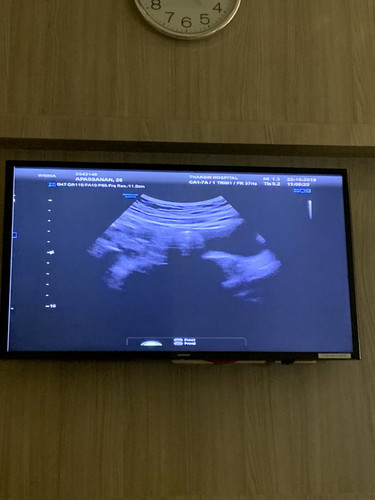

วันนี้ไปอัลตราซาวด์ครั้งแรกมาครับ

ได้ยินเสียงหัวใจเค้าเต้นแล้วดีใจมากครับ